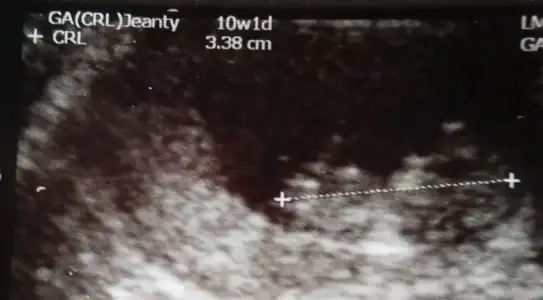

bebegin7-8 haftalıkkenki usg resimine direkt baktıgınızda;

bebek kesenin soluna yakınsa bebek erkek,

sagına yakınsa kız.